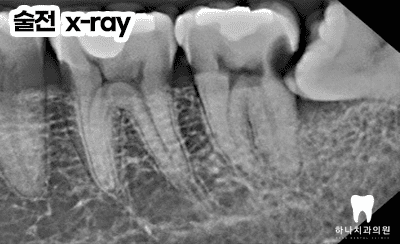

오른쪽 작은 어금니의 치료 과정입니다.

왼쪽의 경우 우식이 숨겨져 있어

잘 보이지 않았으나, 인접면 인레이를

잘 마무리하였습니다.

접근성과 방습에서 매우 어려운

왼쪽 아래 어금니의 치료 과정인데요.

이렇듯 수평으로 매복된 사랑니가

앞쪽 치아의 뒷면에 심한 우식을 발생시켜

발치로 이어지는 경우를 수없이 관찰합니다.

울산삼산동치과에서는 매복 사랑니가 있는 경우,

당장 아프지 않더라도 앞쪽 치아의

우식이 우려된다면 빠르게 발치하는 것이

앞쪽 치아의 건강을 위해 매우 고려되어야

할 사항입니다.

시간이 지체되어 가장 안쪽 어금니의

뒷면에 우식이 발생한 경우

치료가 매우 까다로울 수밖에 없는데요.

우석 우식 부위가 잇몸보다 아래에 위치하고

대부분 처치해야 할 부위가 잇몸뼈의 레벨보다

하방인 경우가 많아 직접적으로 처치하는 것이

수분의 컨트롤과 시야 확보, 기구의 접근성 등에서

거의 불가능에 가깝습니다.